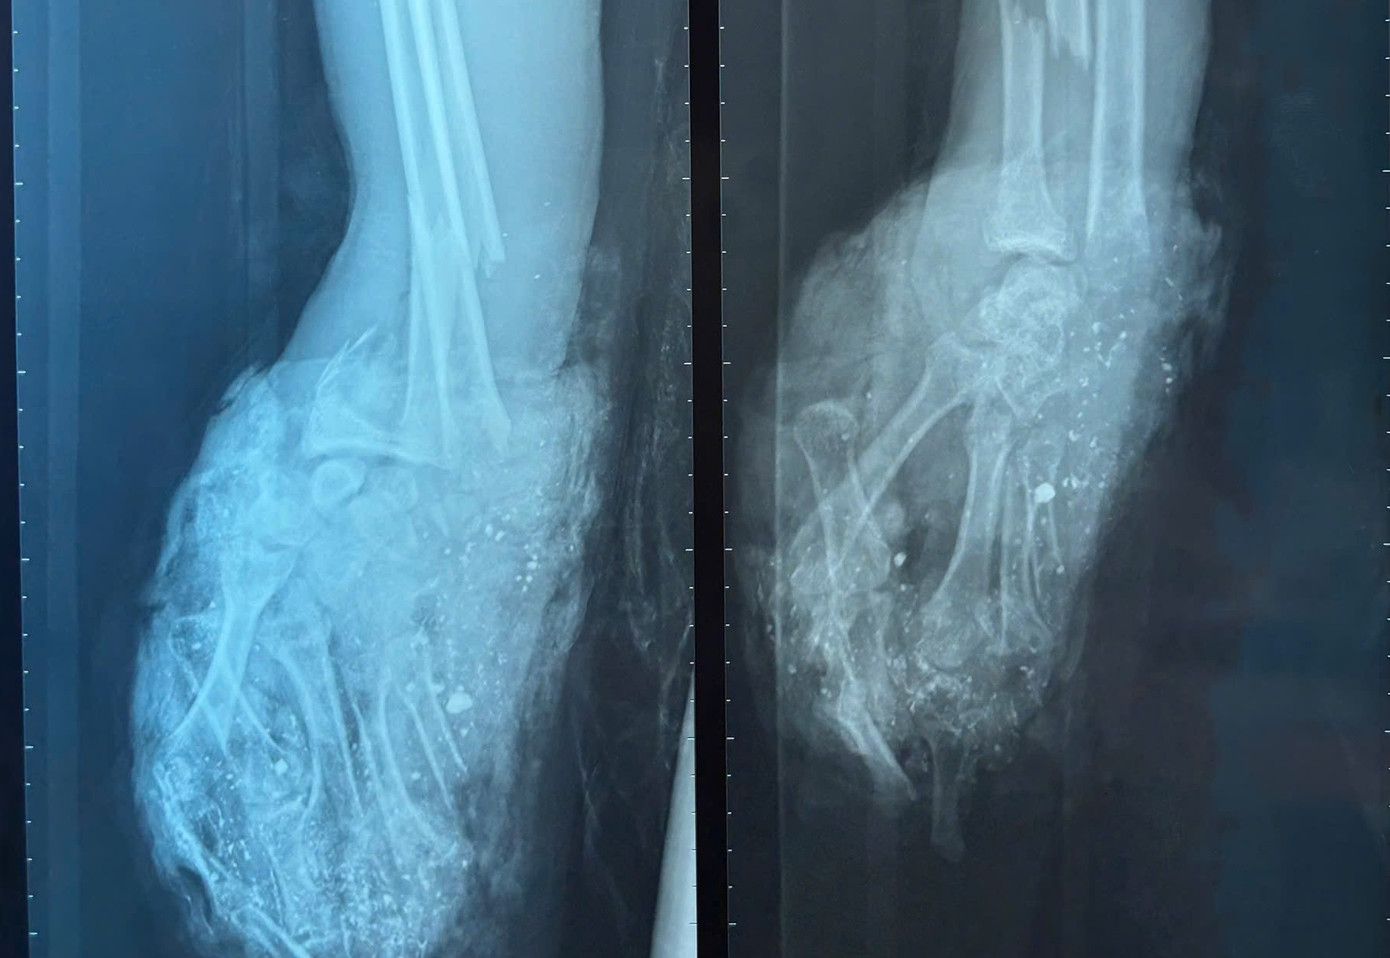

| Bàn tay phải của bệnh nhân dập nát không còn khả năng điều trị bảo tồn |

Trước đó bệnh nhân đã chơi pháo tự chế và bị phát nổ khi đang cầm trên tay. Qua thăm khám và kiểm tra hình ảnh, bác sĩ ghi nhận, bệnh nhân có vết thương phức tạp dập nát bàn tay phải, gãy hở đốt gần ngón I, vết thương ngón II, III, IV bàn tay trái.

Ngay sau khi tiếp nhận bệnh nhân, các bác sĩ đã hội chẩn nhanh và chỉ định thực hiện cuộc phẫu thuật cấp cứu. Bàn tay phải của bệnh nhân bị dập nát phức tạp, không còn khả năng điều trị bảo tồn nên ê kíp bác sĩ đã buộc phải đoạn chi và đóng mỏm cụt ở cổ tay. Bàn tay trái được cắt lọc hoại tử, cố định xương bị gãy, kết hợp xương đốt gần tay cái.